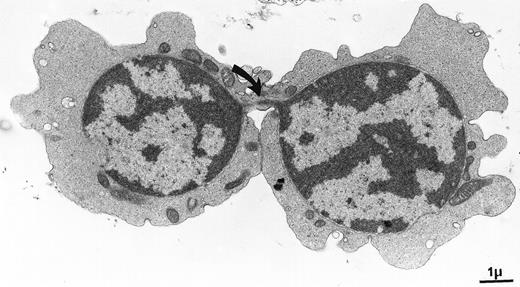

This micrograph shows the thin chromatin bridge linking 2 erythroblasts in a case of congenital dyserythropoietic anemia type I. We used the opportunity to section this characteristic, but rare and discrete, phenomenon. Crossing the bridge was worth the snapshot. . . . . Elisabeth M. Cramer and Josette Guichard, INSERM U.474, Hôpital de Port-Royal, Paris, France.